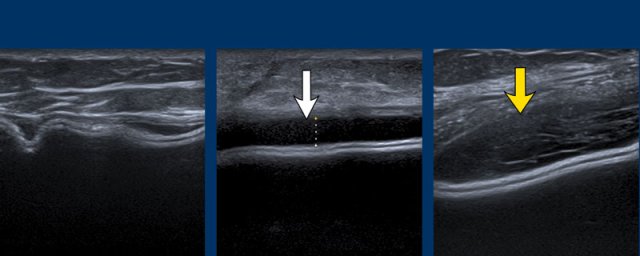

Intracapsular rupture

When the envelope ruptures, but the capsule stays intact, it is called intracapsular rupture.

The Silicone does migrate between the envelope and the capsule, but does not migrate into the breast tissue or beyond.

Signs to look for are:

- Subcapsular sign: Parallel lines within the content of the breast implant, not following the outer envelope-capsular complex.

- Stepladder sign: More layers of parallel lines within the content of the implant.

This sign is similar to the Linguine sign as seen on MR. - Snowstorm artefacts outside the envelope

Stepladder sign

US can detect intracapsular rupture by identifying a series of horizontal echogenic straight or curvilinear lines, somewhat parallel, traversing the interior of the implant, commonly known as the “stepladder sign”.

It is important not to confuse the stepladder sign with normal prominent radial folds.

A. The envelope can no longer be found around the surface of the implant. The inner content is complete inhomogeneous and degenerated.

B. The envelope is collapsed (yellow arrow) and does not follow the outer envelope-capsular complex (white arrow).

There is an inhomogenous collection between the envelope and the capsule containing Silicone. .